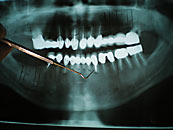

Vor jeder Behandlung steht die Hygiene-, Informations- und Motivationsphase (Prophylaxe). Hier wird das gesamte Gebiss gründlichst gereinigt, Schmutznischen gesäubert und entfernt. Ihnen wird ihr persönliches Reinigungskonzept für ihre Zähne mit auf den Weg gegeben. Damit werden Sie in die Lage versetzt, ihr Gebiss vor und nach abgeschlossener Behandlung zu reinigen. Im weiteren Verlauf einer Parodontitis muss für die Erhaltung eines erzielten Behandlungserfolges Sorge getragen werden. Hierfür ist eine regelmäßige Nachkontrolle in etwa dreimonatigen Abständen unerlässlich.

Liegt nicht eine besonders schwere, akute und aggressive Form der Parodontitis vor, wird immer erst eine konservative und gewebeschonende Behandlung durchgeführt. Diese so genannte geschlossene Kürettage kann auch nach einiger Zeit nochmals wiederholt werden, um das Ausmaß der Taschentiefen weiter zu verringern. Mit speziellen Instrumenten (Küretten, Scalern, slim-line-Ultraschall) werden die Beläge und das entzündete Gewebe in der Zahnfleischtasche entfernt, die Zahnfleischtasche gesäubert und die unter dem Zahnfleisch gelegene Zahnoberfläche geglättet. Dies erfolgt schmerzfrei in lokaler Betäubung.

Bei den sogenannten offenen Kürettagen wird das Zahnfleisch abgeklappt und der Zahn unter Sicht gesäubert. Diese Lappenoperation erfolgt ebenfalls unter lokaler Betäubung. Zusätzlich kann hierbei noch regenerativ gearbeitet werden mit Knochenaufbaumaterial, Membranen, Emdogain etc.